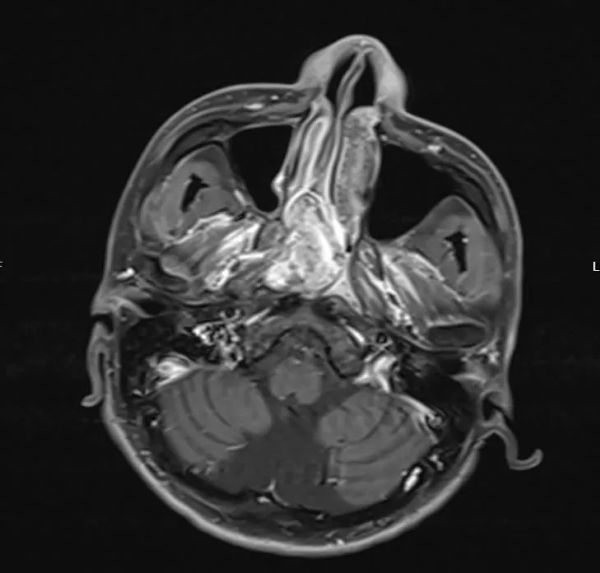

据医院耳鼻咽喉头颈外科医师赵苑介绍,患者因“鼻塞伴张口呼吸”入院,影像学检查发现其鼻咽部存在体积较大的纤维血管瘤,肿瘤血供来自颈外动脉分支,且紧邻颅底结构。鼻咽纤维血管瘤虽属良性,但因其高度血管化特征,术中极易引发大出血,稍有不慎还可能损伤颅神经或引发颅内并发症。此外,患者既往患有线粒体脑病及癫痫,长期服用抗癫痫药物,对麻醉及术后管理提出更高挑战。